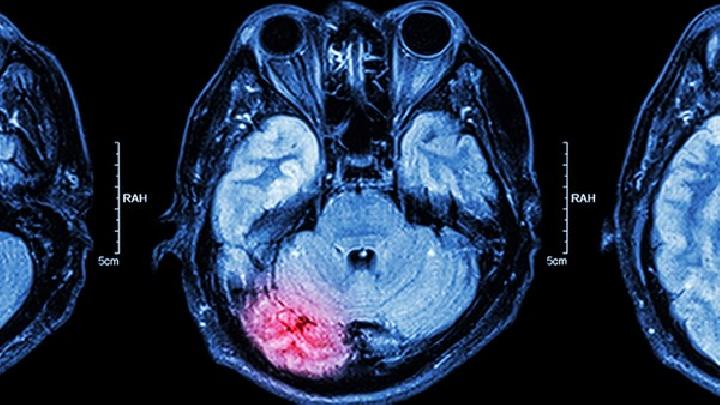

血常规、脑脊液检测、头部MRI、头部CT、、病毒细胞培养